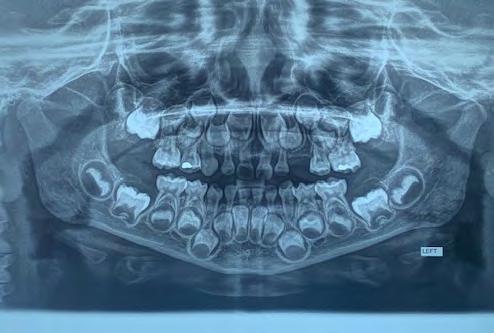

Figura 2. A. Radiografía periapical donde se observa la lesión del odontoma compuesto a nivel del maxilar superior izquierdo. B. Ortopantomografía que revela una lesión radiolúcida unilocular bien definida, con manchas de focos radiopacos, asociada con el canino superior izquierdo temporal impactado de la maxila.

Figura 1. Fotografía de la zona de la lesión en la exploración clínica inicial. Se observa ausencia del canino superior izquierdo, ensanchamiento de la cortical vestibular y aumento de volumen.

A B

El examen clínico reveló un aumento de volumen en la zona de órganos dentarios 63-65 que se extendía al seno maxilar, con desplazamiento de cortical vestibular, sin perforación ni cambio de color en la mucosa, de estructura uniforme bien delimitada. (Figura 1). En el examen radiográfico se observó la expansión de la cortical, con la presencia de múltiples dentículos. Desplazamiento del órgano

175. Marzo 2023 33 Tumores odontogénicos mixtos

Figura 3. Lesión macroscópica

dentario 63 hacia el seno maxilar (Figura 2).

Radiográficamente estas lesiones presentan un área radiolúcida bien definida que contiene cantidades variables de material radiopaco de irregular tamaño y forma. La extensión de las áreas radiopacas y radiolúcidas difieren de una lesión a otra, dificultando muchas veces su diagnóstico radiológico en ocasiones la

cantidad de material mineralizado predomina semejando un odontoma complejo. El tumor puede producir una expansión variable de las corticales y encontrarse asociado a una pieza retenida, a la cual puede desplazar o interferir en su erupción.13

El odontoma compuesto (hamartoma) suele presentarse con mayor incidencia en la región anterior incisivo-canina del maxilar,17 coincidiendo con el presente caso, se puede establecer que la radiografía panorámica es una herramienta muy útil, para contribuir en el diagnóstico